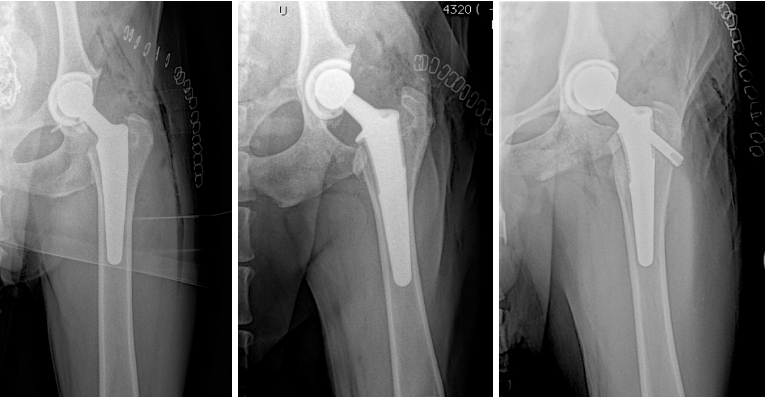

These are nice examples of Biomedtrix BFX cementless femoral stems. From left, the original tapered stem design to the newer, augmented collared (middle image) and lateral bolt (right) femoral stems.

This is an example of a German Shepherd dog with bilateral, hybrid, total hip replacement (Biomedtrix BFX cementless acetabular cup and CFX cemented femoral stem). Hybrid constructs may be used in certain breeds like the German Shepherd and giant breed dogs, geriatric dogs or those with poor bone quality/thin femoral cortices.